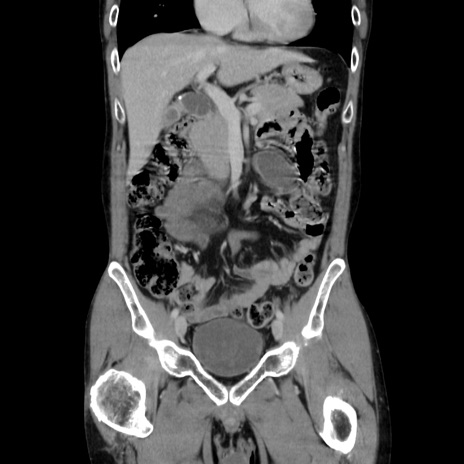

症例37(冠状断像)

【症例】40歳代 男性

【主訴】腹痛

【現病歴】4時間ほど前に電車に乗車中に臍部上より腹痛出現。徐々に増悪し起立困難となり、救急外来受診。生ものは数日食べていない。今朝お雑煮を食べた。

【身体所見】BT 36.8℃、BP 117/84mmHg、HR 91/min、SpO2 97%、苦悶様、腹部:臍上部広範囲圧痛あり、反跳痛±

【データ】WBC 8100、CRP 0.03